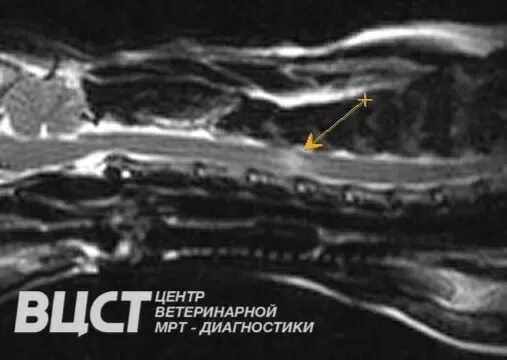

Фиброзно хрящевая эмболия у собак